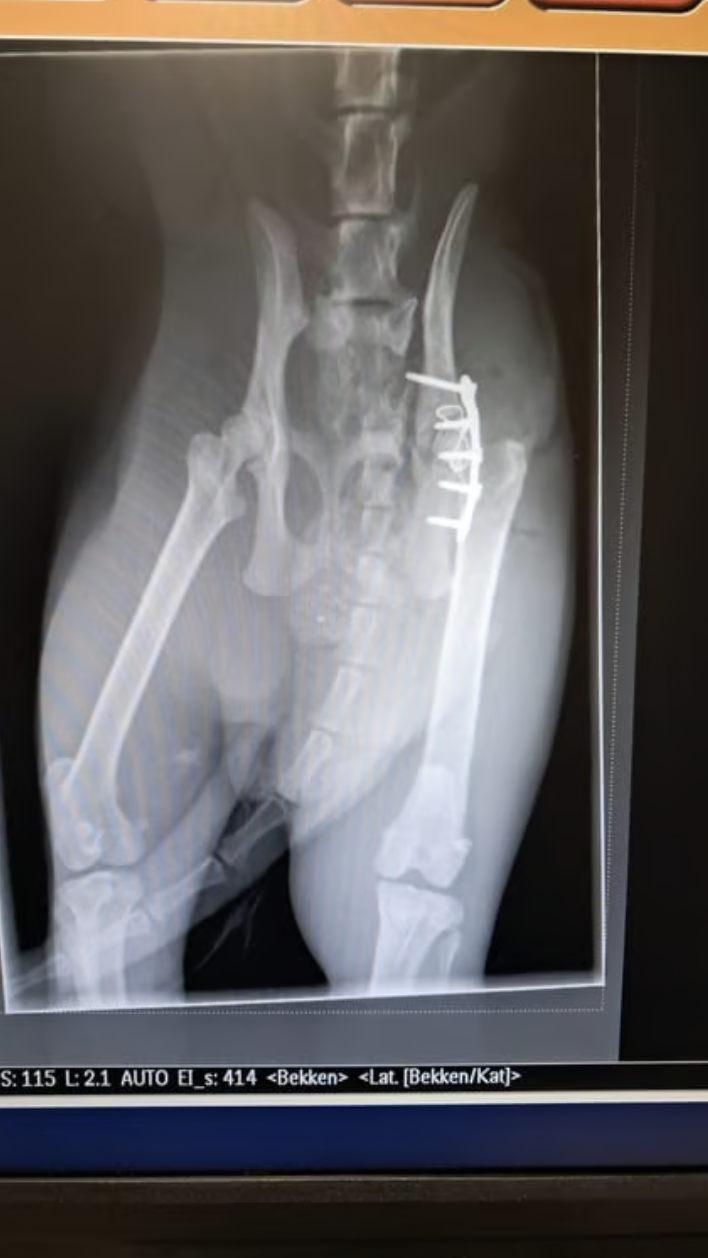

Röntgenfoto

Willem kreeg het zwaar voor de kiezen, want hij werd aangereden door een auto. Het gebeurde op 22 maart op de Prins Bernhardlaan in Voorburg. De automobilist reed door, maar een omstander belde de dierenambulance. "Zijn bekken was gebroken, de heupkop gescheurd en een heleboel botten waren van hun plek."